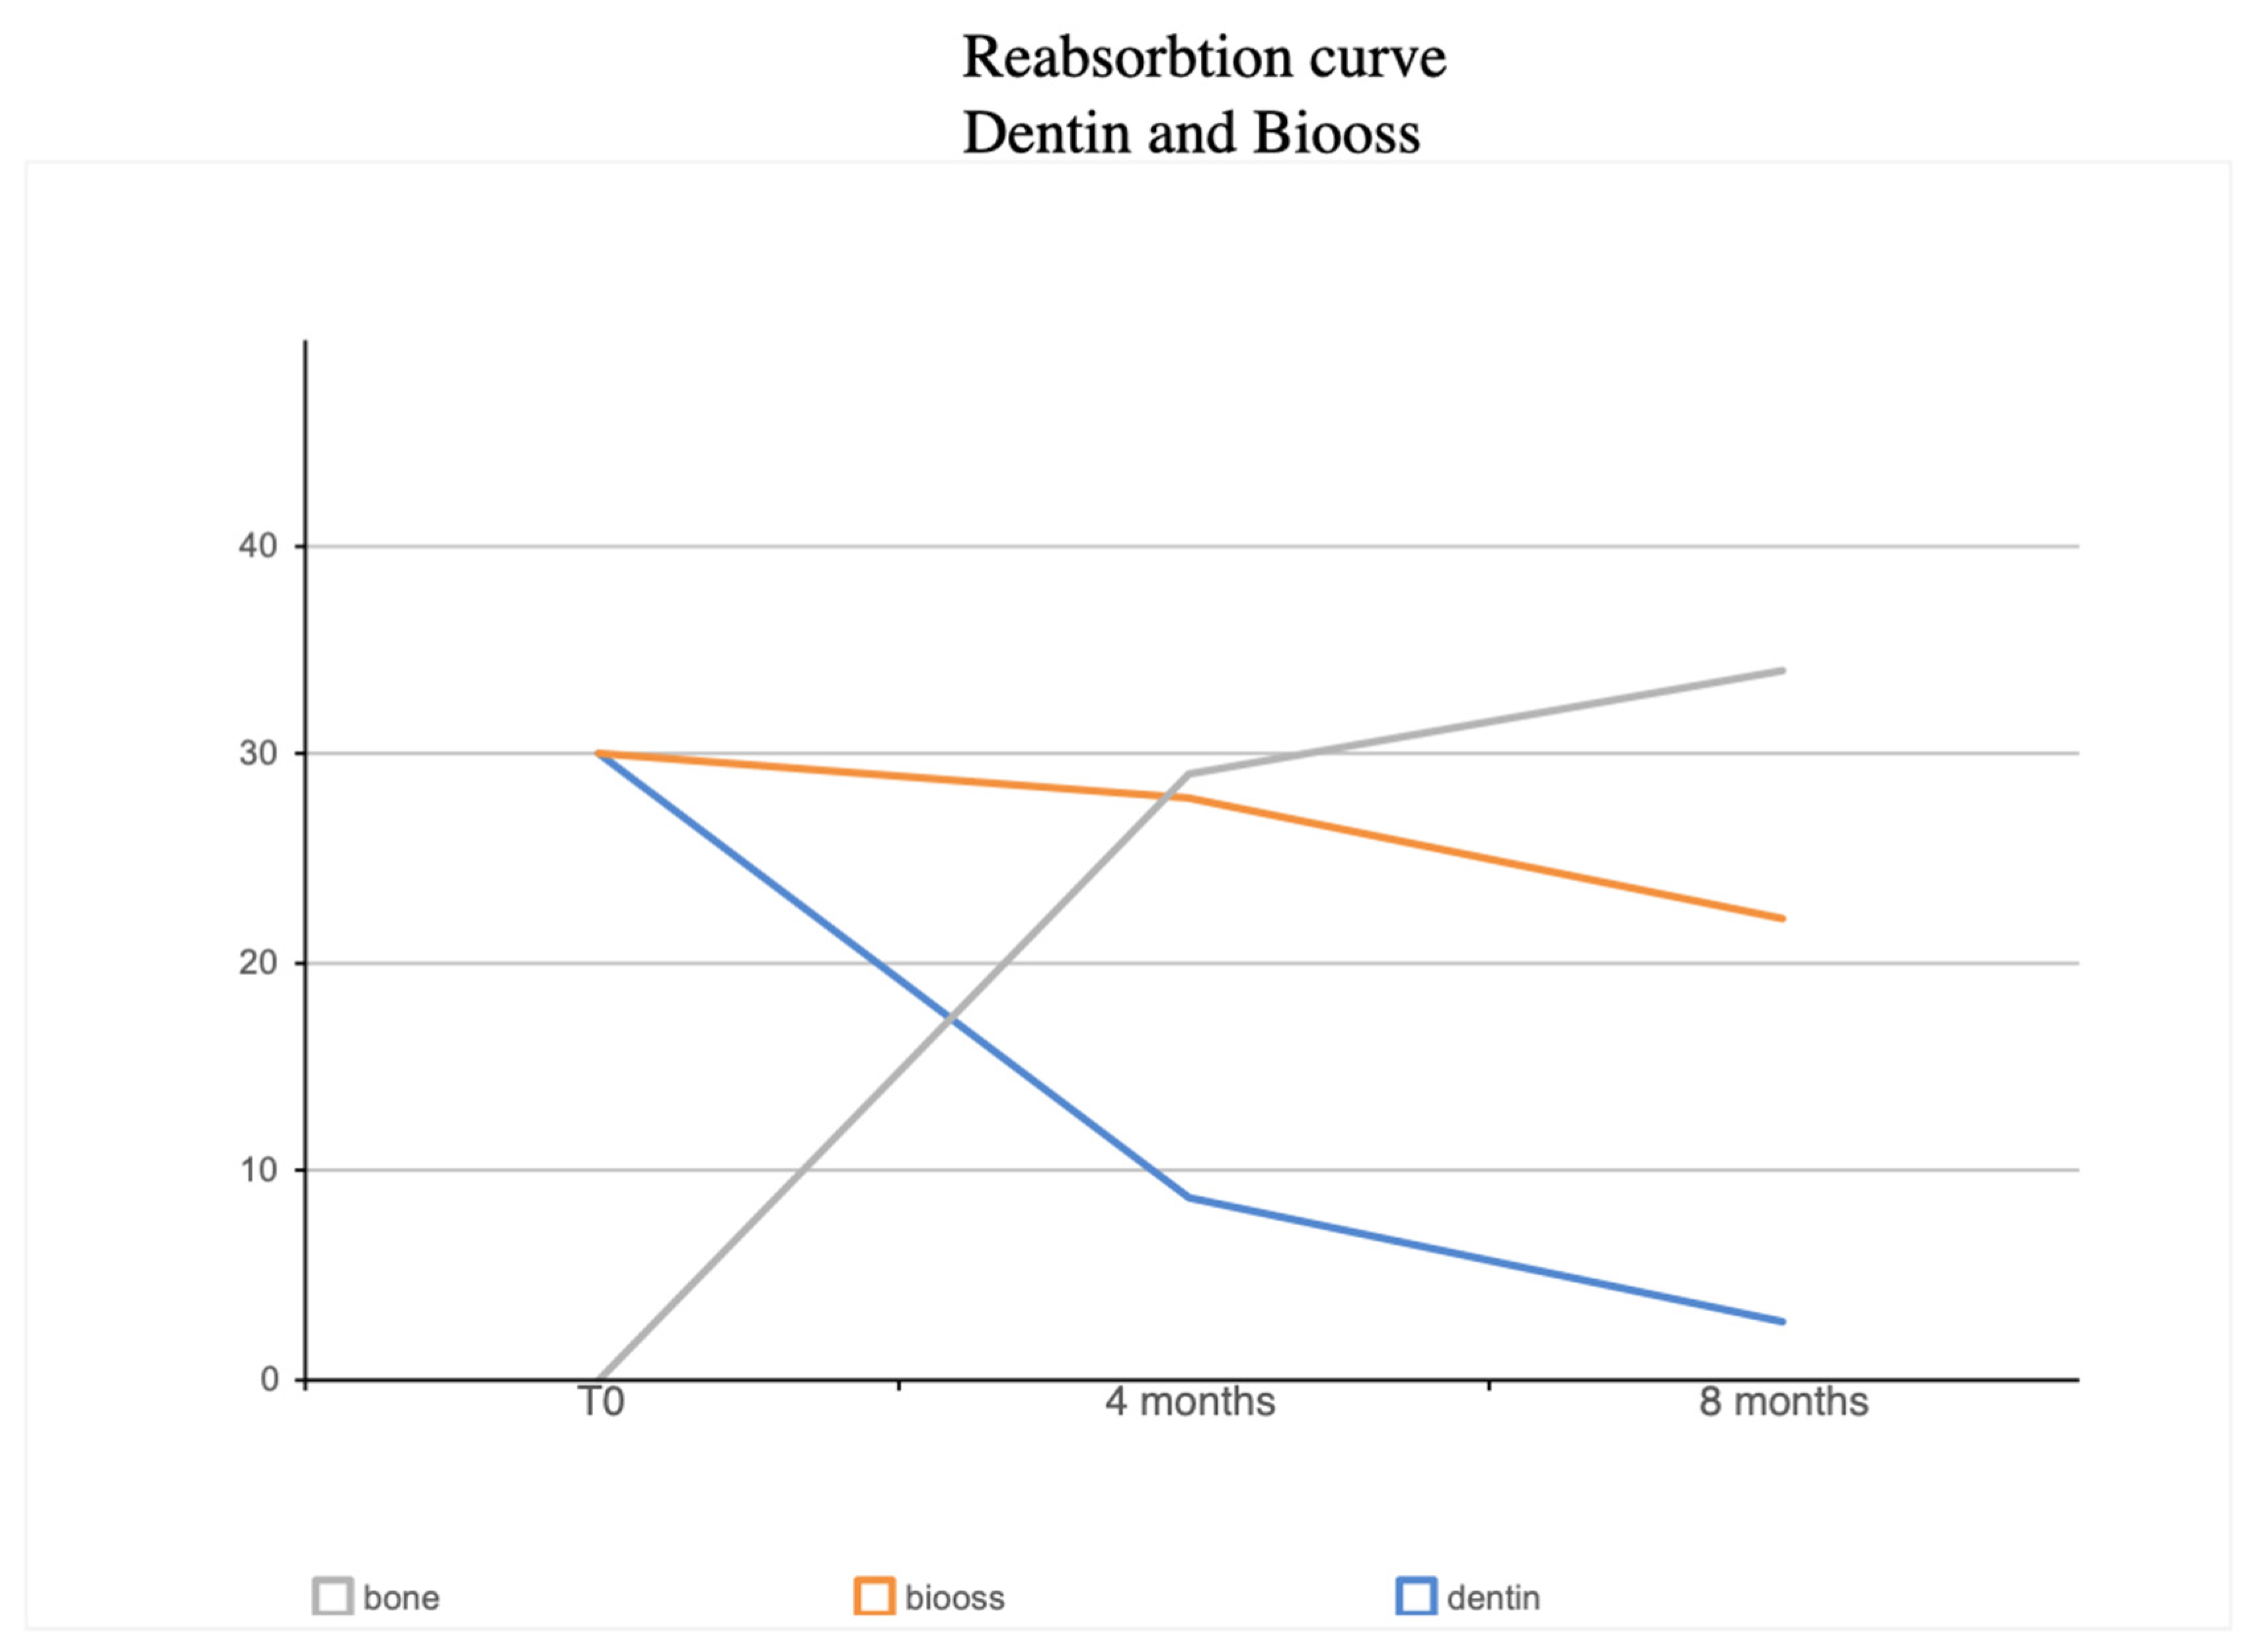

3. Results

4. Discussion

| BV% | NB% | Residual Graft Dentin % | Dentin Loss Percentage | Residual Graft Bio-Oss % | Bio-Oss Loss Percentage | |

|---|---|---|---|---|---|---|

| 4 Months | 65.66% | 29.03± 6.57% | 8.68 ± 3.36% | 71% | 27.95 ± 5.23% | 6.74% |

| 8 Months | 59% | 34.12 ± 5.05 | 2.79 ± 1.48 | 90.71% | 22.09 ± 13.81 | 26.42% |